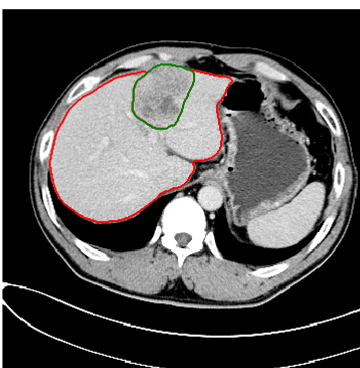

本次肝脏分割挑战赛的难点在于,相比于正常的器官,肿瘤没有固定的形状、大小和纹理,因此CT图像中肝脏肿瘤的分割极具挑战性。对此,沈超敏团队精心设计了数据预处理和3D神经网络的自动分割方法,使得肝脏及肝脏内的肿瘤均达到理想的精度。下面两图是肝脏与肿瘤的分割效果图,红色线段为肝脏区域边缘、绿色为肿瘤区域边缘。

图1 图2